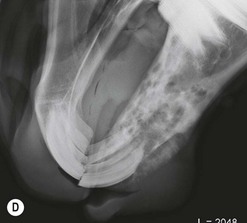

Clinical features

The condition is usually presented as a painful, hot, progressive swelling of the mandible with a characteristic ‘sun-burst’ radiographic appearance of bone lysis and irregular deposition of trabecular reactive new bone44 (Fig. 11.12). Pathological fractures can occur in affected bones.

image image image image image

Fig. 11.12 (A) & (B) This 5-year-old Irish Draught mare was presented with a 4-week history of a mandibular swelling, gingival bleeding, weight loss and dysmasesis. The mandibular incisors were palpably loose and the mandible was warm to the touch and mildly painful on palpation. (C) & (D) Lateral and occlusive radiographs gave the suspicion of a neoplastic lesion. (E) A bone biopsy was taken from several sites, and the horse was diagnosed with osteosarcoma.

Diagnostic confirmation

Their radiographic appearance is highly suggestive, but biopsy provides the only definitive diagnosis. There is a characteristic combination of cortical bone destruction and periosteal new bone formation giving the area a ‘sunburst’ radiographic appearance.

Bone biopsies of osteosarcoma are sometimes easy to obtain, since the bone is usually softer than normal and the medullary cavity is filled with diagnostically significant friable pink to white material containing variable amounts of cancellous bone (Fig. 11.12E). It is easy to miss tumor tissue in small bone biopsies, and florid, non-neoplastic reactive bone or fracture callus can easily be mistaken histologically for neoplasia. Multiple biopsies should, therefore, be collected from sites identified by radiography or CT or MR imaging methods, but this is not an easy procedure.